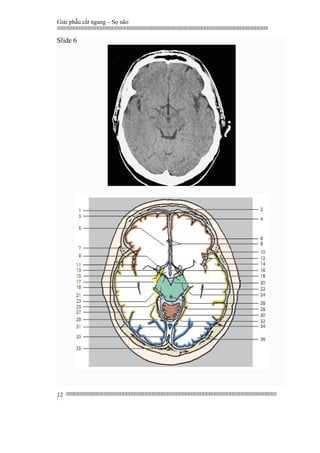

Slide 6

1. Frontal bone

2. Frontal sinus

3. Falx cerebri

4. Superior frontal gyrus

5. Cingulate gyrus

6. Middle frontal gyrus

7. Inferior frontal gyrus

8. Interior cerebral artery

9. Striatum (inferior portion)

10. Lateral sulcus (insularcistern)

11. Insula

12. Insular arteries

13. Optictract

14. Superior temporal gyrus

15. Hypothalamus

16. Third ventricle

17. Cerebral peduncle

18. Parietal bone

19. Lateral ventricle (temporalhorn)

20. Interpeduncular cistern

21. Middle temporal gyrus

22. Hippocampus

23. Parahippocampal gyrus

24. Ambient cistern

25. Mesencephalon (quadrigeminal

plate)

26. Aqueduct

27. Inferior temporal gyrus

28. Quadrigeminal cistern

29. Lateral occipitotemporal gyrus

30. Vermis of cerebellum

(superior portion)

31. Parieto-occipital sulcus

32. Tentorium cerebelli

33. Superior sagittal sinus

34. Straight sinus

35. Occipital bone

36. Occipital gyri

1. Xương trán

2. Xoang trán

3. Liềm não

4. Hồi trán trên

5. Hồi viền

6. Hồi trán giữa

7. Hồi trán dưới

8. Động mạch não dưới

9. Thể khía (phần dưới)

10. Rãnh bên (bể thuỳ đảo)

11. Thuỳ đảo

12. Các động mạch thuỳ đảo

13. Hệ thống nhãn cầu

14. Hồi trên thái dương

15. Đồi thị

16. Não thất ba

17. Cuống não

18. Xương đỉnh

19. Sừng thái dương não thất bên

20. Bể gian cuống não

21. Hồi thái dương giữa

22. Hồi hải mã

23. Hồi cạnh hải mã (hồi thái dương)

24. Bể tĩnh mạch não lớn

25. Mãnh não (mãnh sinh tư)

26. Cống não

27. Hồi thái dương dưới

28. Bể mãnh não sinh tư

29. Hồi chẩm thái dương bên

30. Thuỳ giun, thuỳ nhộng

(phần trên)

31. Khe đỉnh – chẩm

32. Lều tiểu não

33. Xoang dọc trên

34. Xoang thẳng

35. Xương chẩm

36. Hồi chẩm